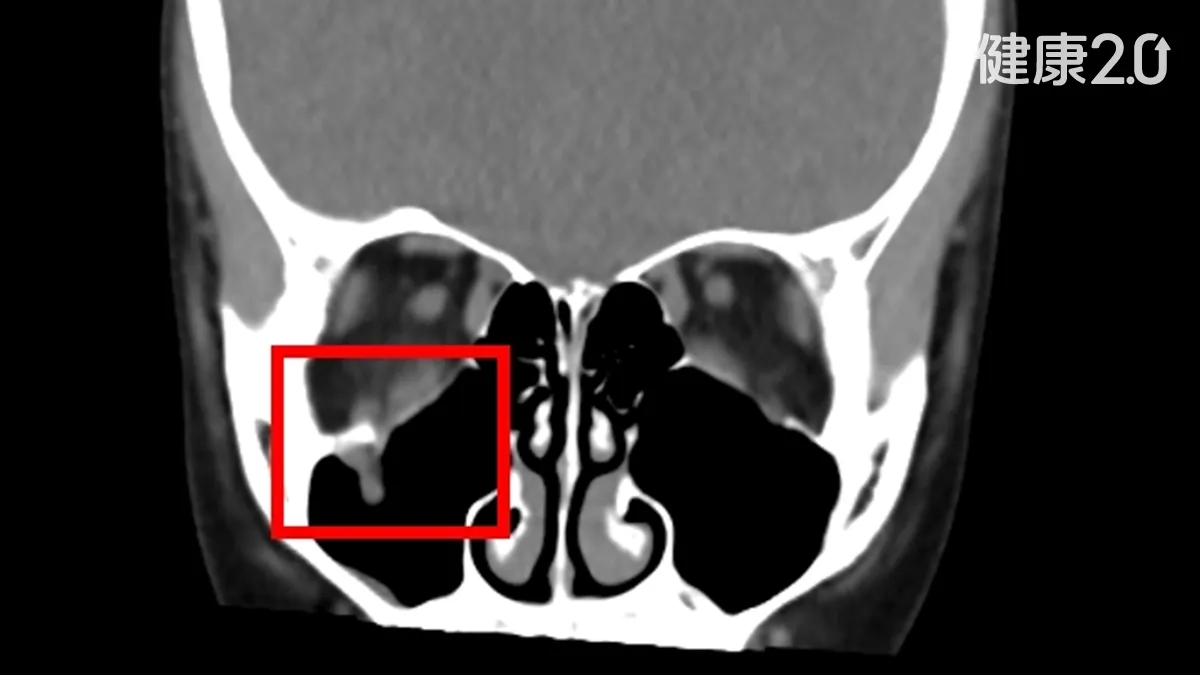

王姓女童眼周被同學的膝蓋撞到後,本來沒有察覺視力出問題,眼周外觀也沒有瘀青、腫脹,直到事發2個多星期後,女童向家長反映看東西有影子,眼睛動不了,右眼往上看只能看向左上方,才緊急就醫,被診斷眼眶底骨發生「線性爆裂性骨折」。

邱昱瑋說,比較需要注意的是,兒童的骨頭相對柔軟,因此眼眶底骨更容易發生「線性爆裂性骨折」,有如門片回彈復位,會把眼眶內的肌肉或其他軟組織夾在骨折的縫隙中,導致視覺上產生複視、眼球運動受限,視線無法自由移動,最危險的是小朋友眼窩骨折不會有明顯瘀青、紅腫,因此容易被忽略。

王小妹就醫時距離事發已經超過2周,中山附醫口腔顎面團隊立即為她制定手術方案,利用創新電腦數位模擬,搭配內視鏡和精密導航系統,精準定位被骨折縫隙夾住的肌肉位置,成功把被夾住的眼底肌肉回歸原位,術後女童的複視症狀消失,眼球活動恢復正常,沒有出現併發症。